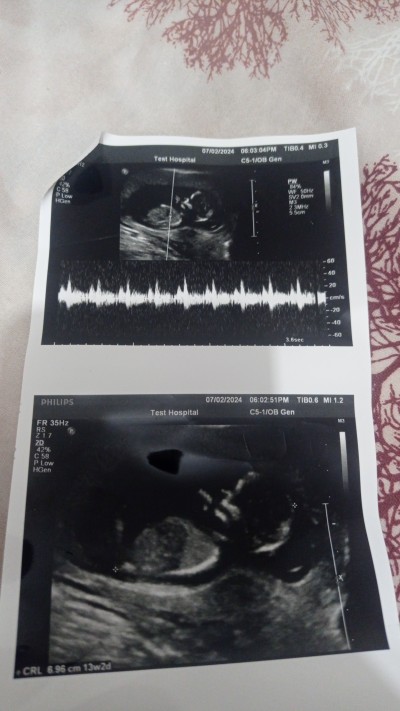

arkadaşlar sadece merak için soruyorum tabiki başta sağlıkli olması önemli benim için sizde tahminde bulunurmusunuz doktor bir kız Bir oğlan diyor şaşırdım bende

İki bacak arası gözükmüyor böyle anlaşılması zor

İki bacak arasi videodan çektim

Kıza benziyor bos